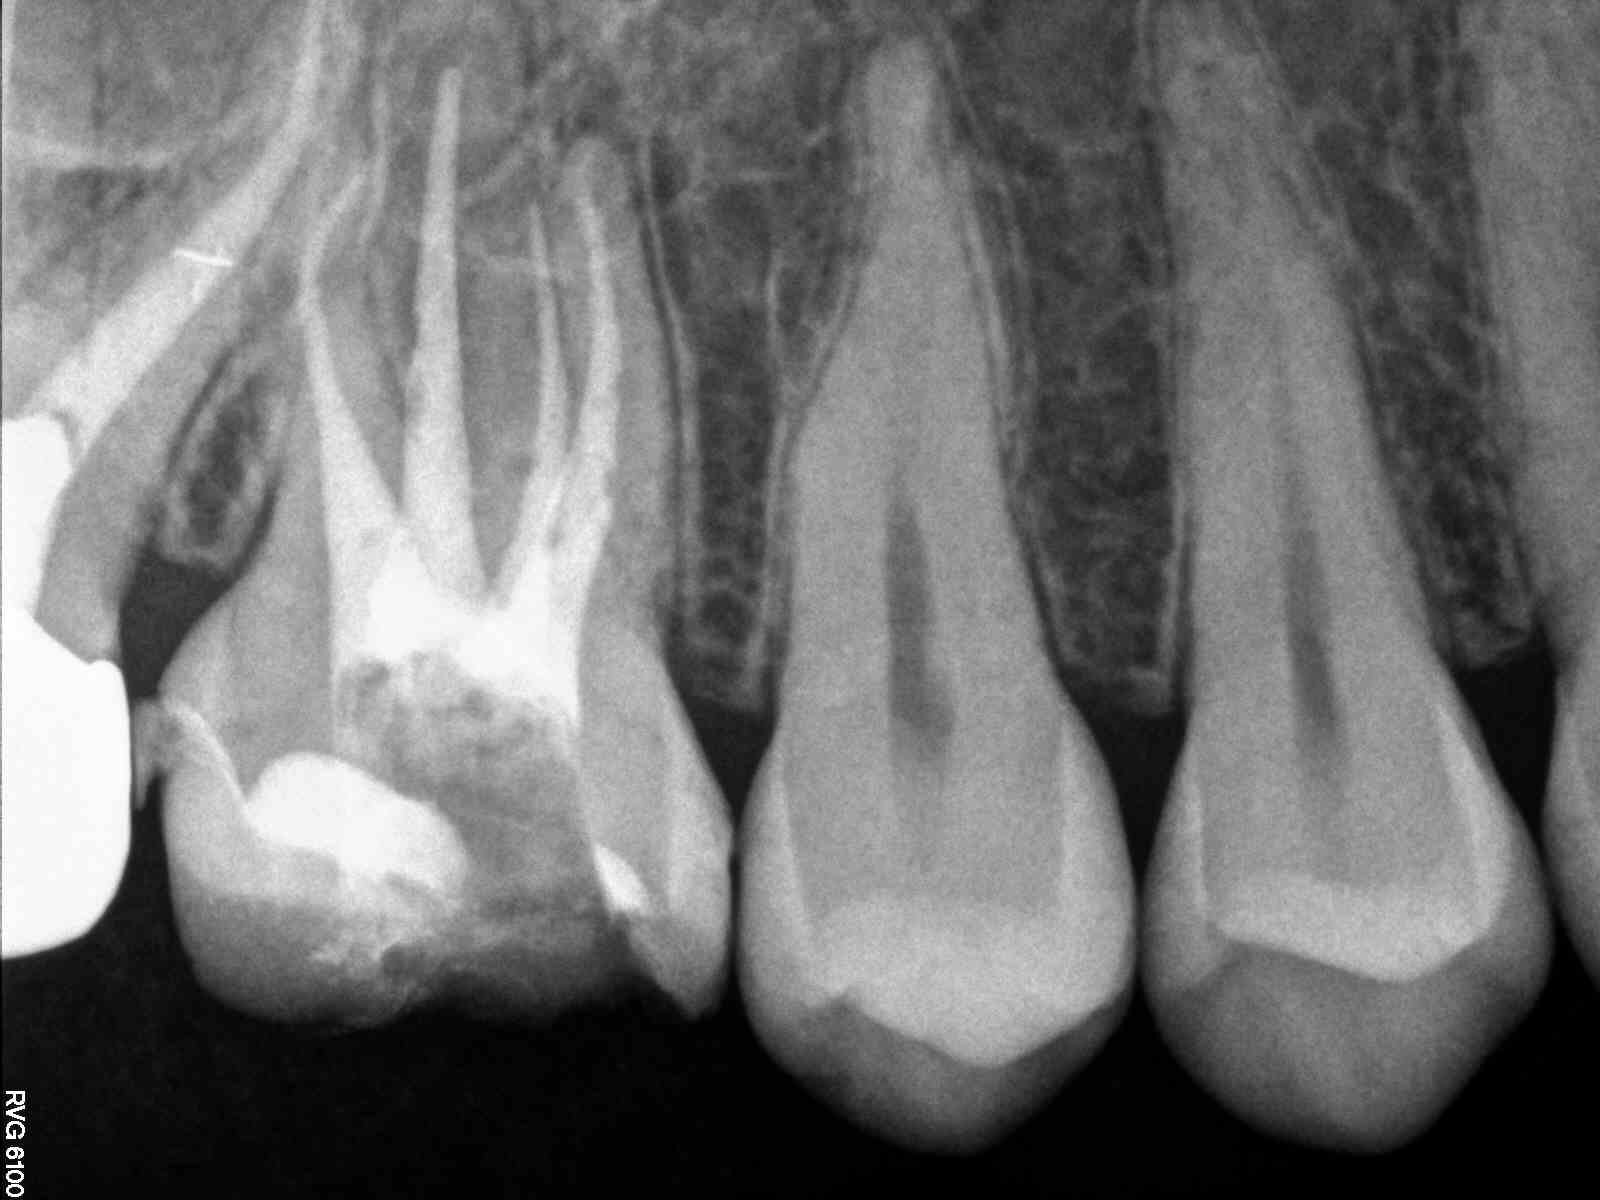

# teeth with MB2 present- able to cleanse and shape the MB2 – MB2 join

MB1 – teeth I consider calcified that no MB2 was found – total # of 1st

molar treated

MB2 distance from MB1 – join MB1

5-2

6-5-1-0-7

1 mm or less—-no